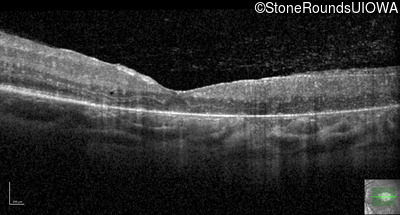

Optical Coherence Tomography - Right - 20/160

Exemplar / OCT Stack